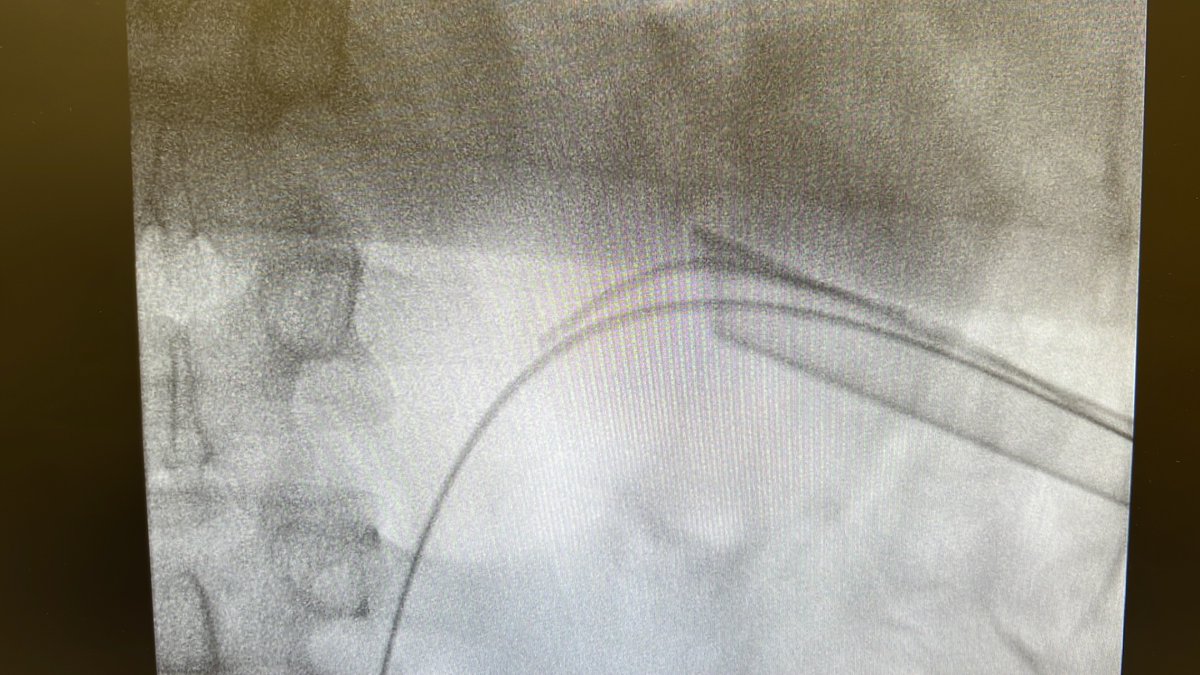

The Road Not Taken-Robert Frost Endourology Variant Two roads diverged in a yellow tube I shall be telling this with a sigh And I Am glad I put the dye ! The importance of doing retrograde in acute obstructing stone !